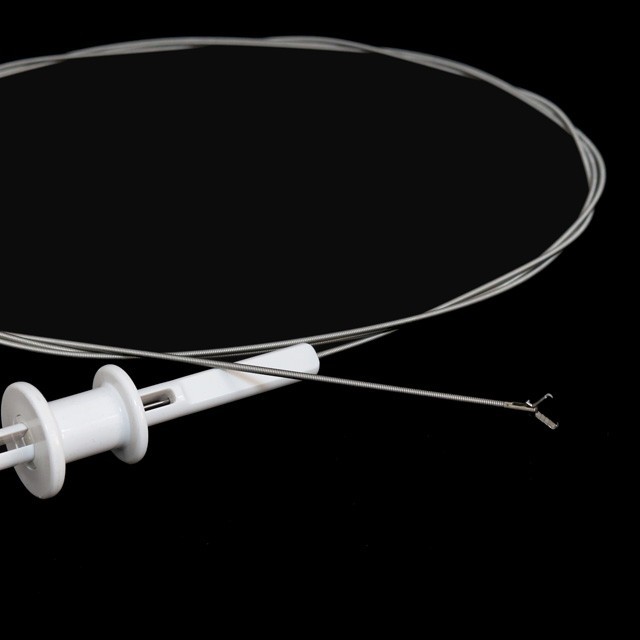

پروگ قسم

fg -28 U-b3 |

2.3 |

2.8 کان وڌيڪ يا برابر آهي |

2300 |

3- پرگ قسم |

fg -28 U-b4 |

2.3 |

2.8 کان وڌيڪ يا برابر آهي |

2300 |

4- پرگ قسم |

fg -28 U-b5 |

2.3 |

2.8 کان وڌيڪ يا برابر آهي |

2300 |

5- پرگ قسم |